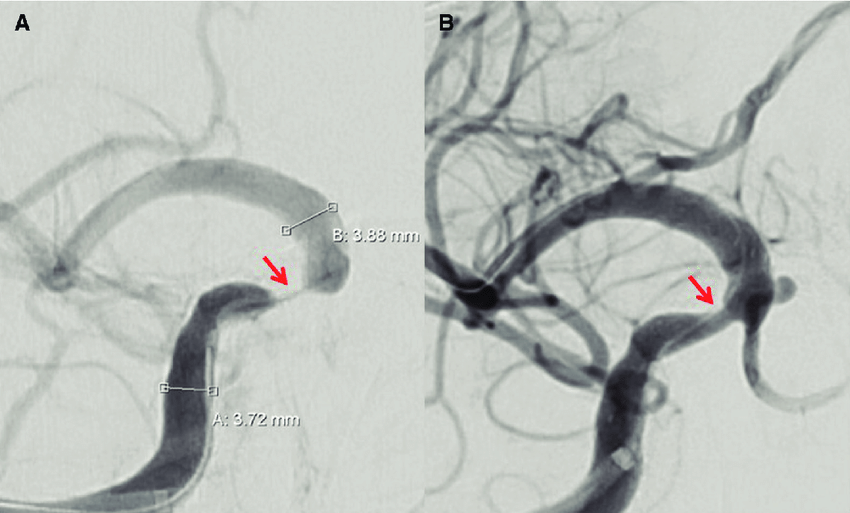

En los pacientes con accidente isquémico transitorio o accidente cerebrovascular isquémico debido a estenosis aterosclerótica intracraneal grave sintomática, la adición de angioplastia transluminal percutánea y colocación de stent al tratamiento médico, en comparación con el tratamiento médico solo, no produjo diferencias significativas en el riesgo de accidente cerebrovascular o muerte. JAMA, 9 de agosto de 2022.